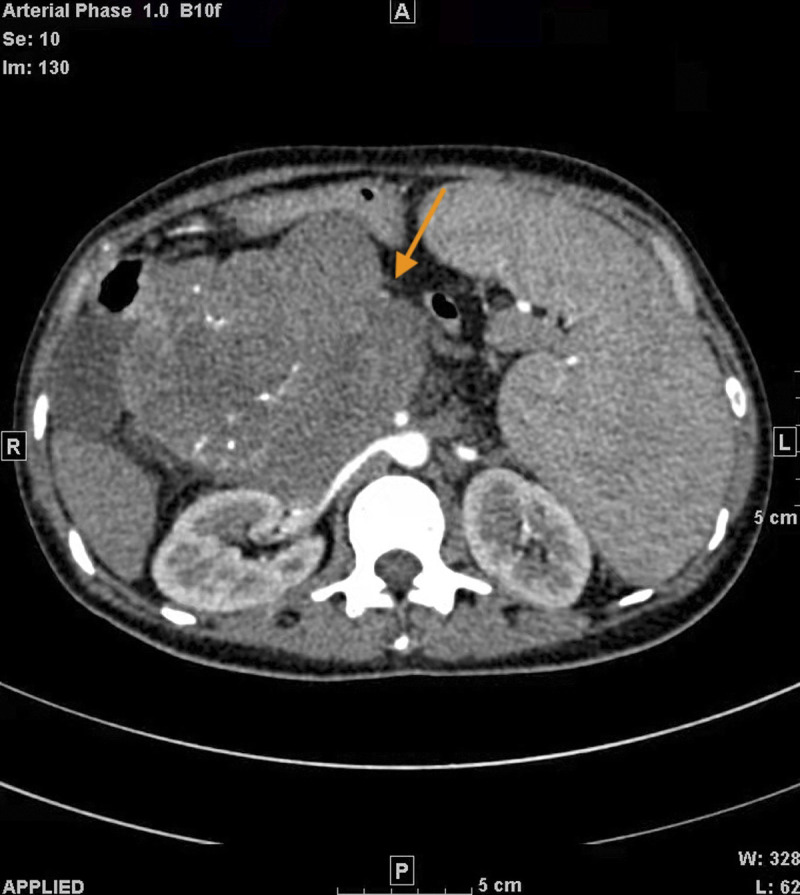

Pregnancy with solid pseudopapillary tumor of the pancreas (SPTP) is rare. Because pregnancy hormones may cause tumor progression, the management and treatment of SPTP need to balance the safety of pregnant women and fetuses with surgical treatment. We reported a case of a giant pancreatic tumor diagnosed during pregnancy that was considered to be SPTP. Examinations also showed hepatitis B virus infection and severe decompensation of liver cirrhosis. Medical termination of pregnancy was performed. The patient has lived with the tumor until now without surgery. We retrieved the published case reports, summarized the clinical characteristics of pregnancy with SPTP, and explored its management during the perinatal period. Most patients with SPTP have a good prognosis with good maternal and fetal outcomes, and it is important to choose an appropriate treatment method and timing. However, pregnancy combined with decompensated liver cirrhosis needs to be terminated in a timely manner because of its high-risk status.